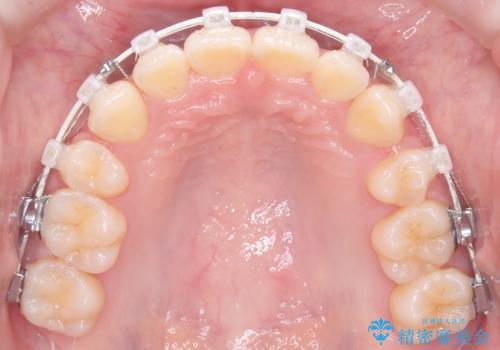

精密検査の結果、歯を並べるスペースの不足に加え、上下の歯列の正中(中心)が大きくズレていることが確認されました。突出した口元を下げ、顎の左右バランスを整えるためのスペースを確保するため、右上・左上・左下の4番目(第一小臼歯)を計3本抜歯する計画を立案。装置は、治療中の見た目にも配慮し、目立ちにくい審美ワイヤーを選択しました。

治療は、抜歯によって得られたスペースを活用し、前歯を後方へ移動させながら上下の中心を一致させる緻密な調整を行いました。

特に下顎の右方偏位に対しては、ワイヤーによる繊細なコントロールを行い、左右の咬合バランスを整えることに重点を置きました。2年半の治療期間を経て、突出していた前歯は理想的な位置に収まり、顎のズレも大幅に改善されました。